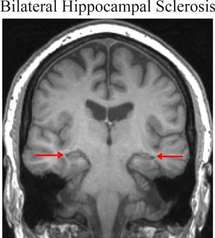

Imagen del cerebro de un paciente con esclerosis bilateral del hipocampo. El hipocampo está indicado por las flechas y es más pequeño que un hipocampo normal. Fuente: UCL.

Normalmente, la amnesia suele estar ocasionada por daños en una región del cerebro llamada hipocampo. Se sabe que esta región, que está situada en los lóbulos temporales, está involucrada en la memoria a largo plazo, la memoria espacial y los desplazamientos físicos. También es una de las primeras zonas afectadas por la enfermedad de Alzheimer, cuyos síntomas son las deficiencias de memoria y la desorientación.